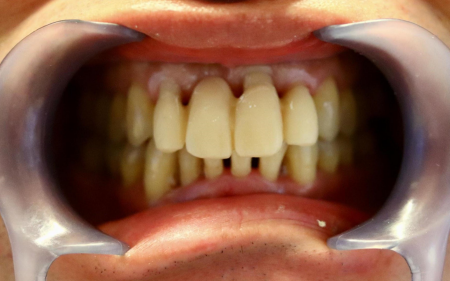

治療後

また、最終的な被せ物に仮歯の形を反映させるため、被せ物を作製する「ラボ」にて仮歯の形をデジタルスキャンし、自然な白さの被せ物「ジルコニアブリッジ」を作製しました。

完成したジルコニアブリッジを実際に装着して噛み合わせを調整し、エアーフローで接着面を清潔にした後に、歯科用の接着剤「ジーセムone」で接着して治療を終了しました。